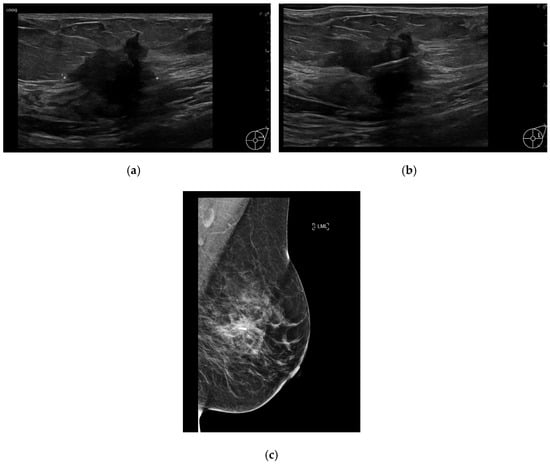

The RFID tags were inserted by either a consultant breast radiologist or a breast radiology trainee under ultrasound or mammographic guidance (Figure 1a–c). RFID tag insertion was performed during a dedicated appointment prior to surgery, allowing for preoperative planning and minimizing logistical challenges on the day of surgery. The LOCalizer™ system comprises a unique RFID tag, which measures approximately 11 mm in length and 2 mm in diameter, deployed using a 12-gauge introducer. Each RFID tag includes a polypropylene cap designed to prevent migration within the breast tissue, ensuring stability throughout the preoperative period. After RFID tag insertion, a handheld portable reader displays the distance to the RFID tag in millimeters, which is particularly valuable when deploying more than one RFID tag (e.g., in cases of bracketing or multifocal disease). The system also assigns an individual ID RFID tag number, which is recorded in the patient’s medical notes (Figure 2a,b), facilitating accurate intraoperative retrieval.

Figure 1. (a) Ultrasound of the left breast demonstrates a 25 mm hypoechoic, irregular lesion within the upper outer quadrant, which was also noted to have internal vascularity. Biopsy results yielded invasive ductal carcinoma (grade 3). (b) Ultrasound image obtained during localization shows a RFID tag deployed within the center of the lesion. (c) Mediolateral oblique view post-localization mammogram of the left breast shows successful RFID tag placement within the center of the lesion.